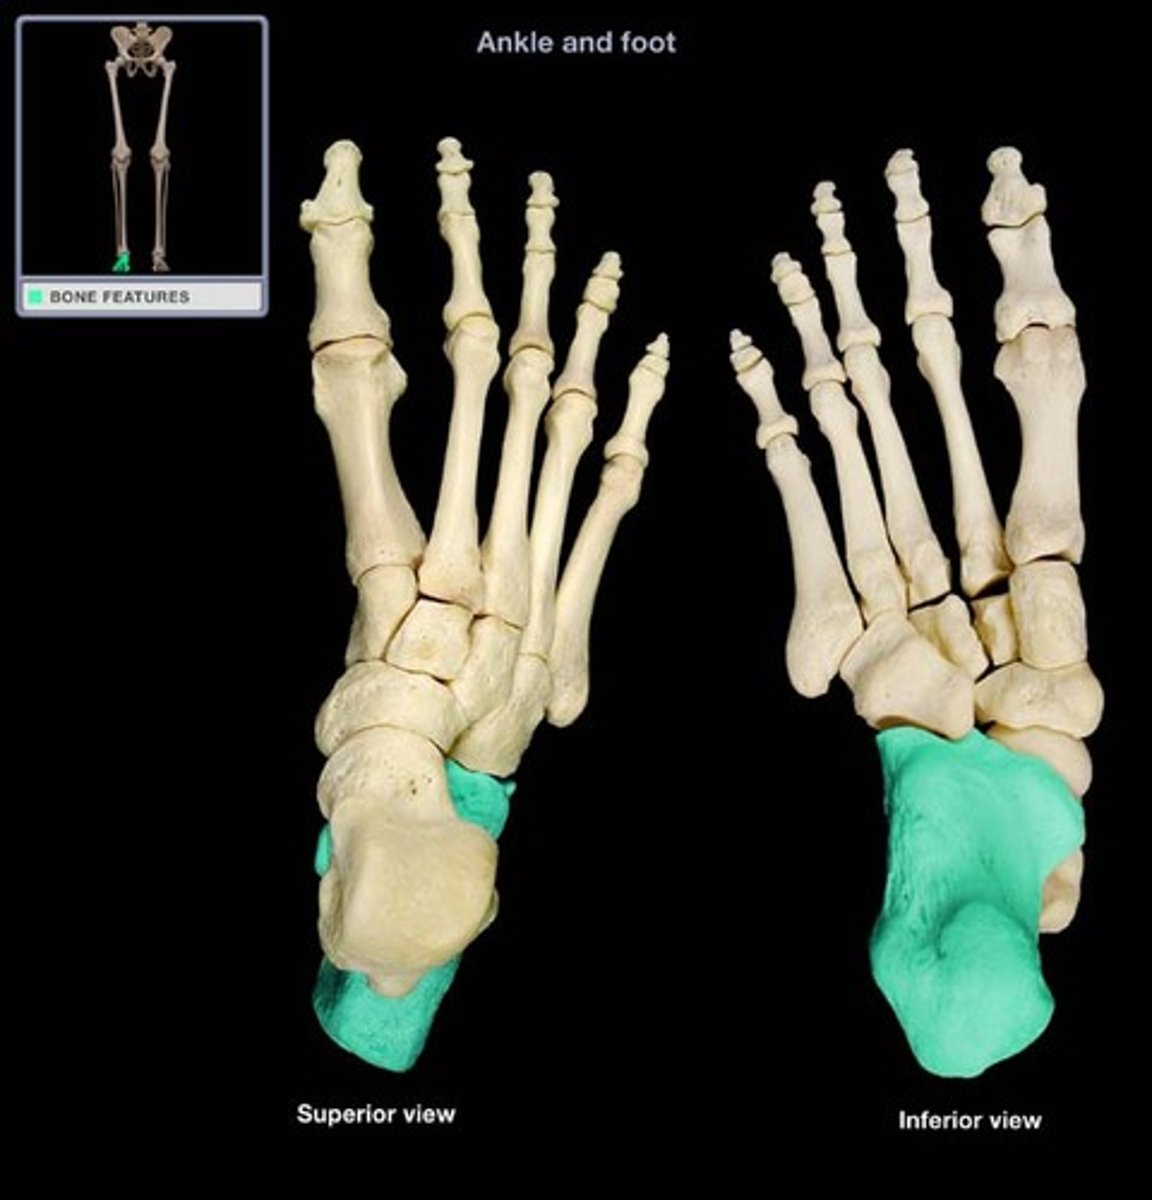

calcaneus